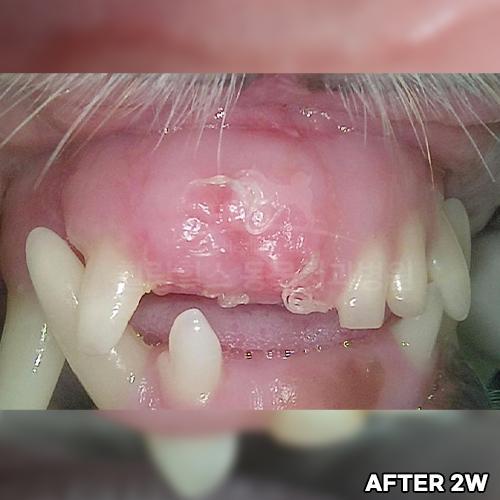

강아지잇몸에혹! Ossifying fibromatous epulis (골화성 섬유종성 치은종)! 강아지치은종 수술 전 후 모습 - 힐링힐스동물치과병원 -